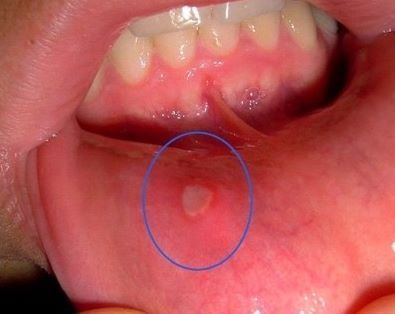

이 고통 아는사람 손

알보칠이 짱이에요 알보칠 바르면 금방 나아요

아 지금 저거 두배만한거 생김 으엉우어엉어너 아므것도 못하겠어요 무기력해짐